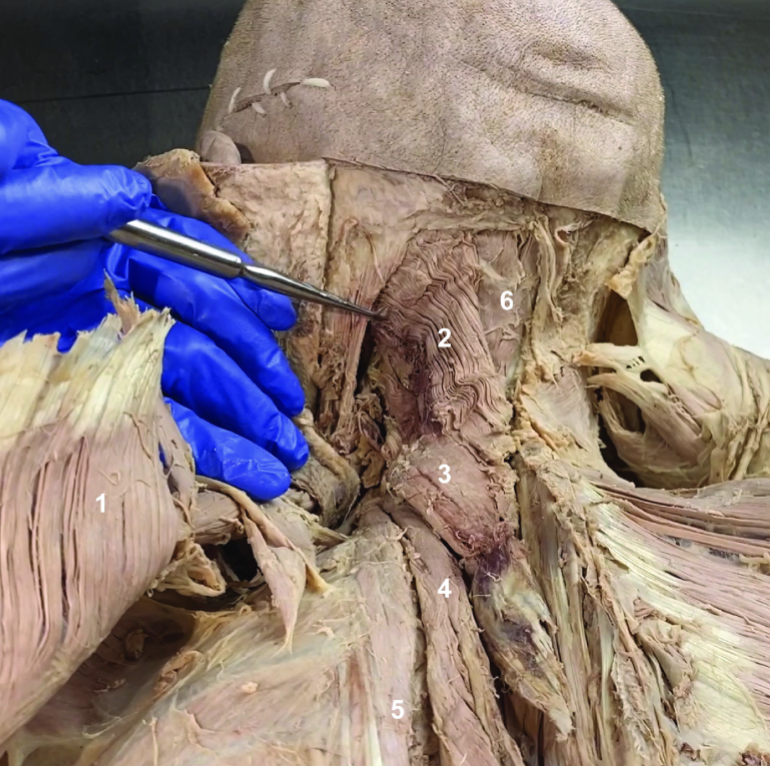

Trapezius (reflected)

ID structure

Spinal accessory n. (CN XI)

ID structure

Transverse cervical a.

ID structure

Levator scapulae

ID structure

Rhomboid minor

ID structure

Rhomboid major

ID structure

Rhomboids (reflected)

ID structure

Splenius capitis

ID structure

Splenius cervicis

ID structure

Longissimus

ID structure

Iliocostalis

ID structure

Semispinalis capitis